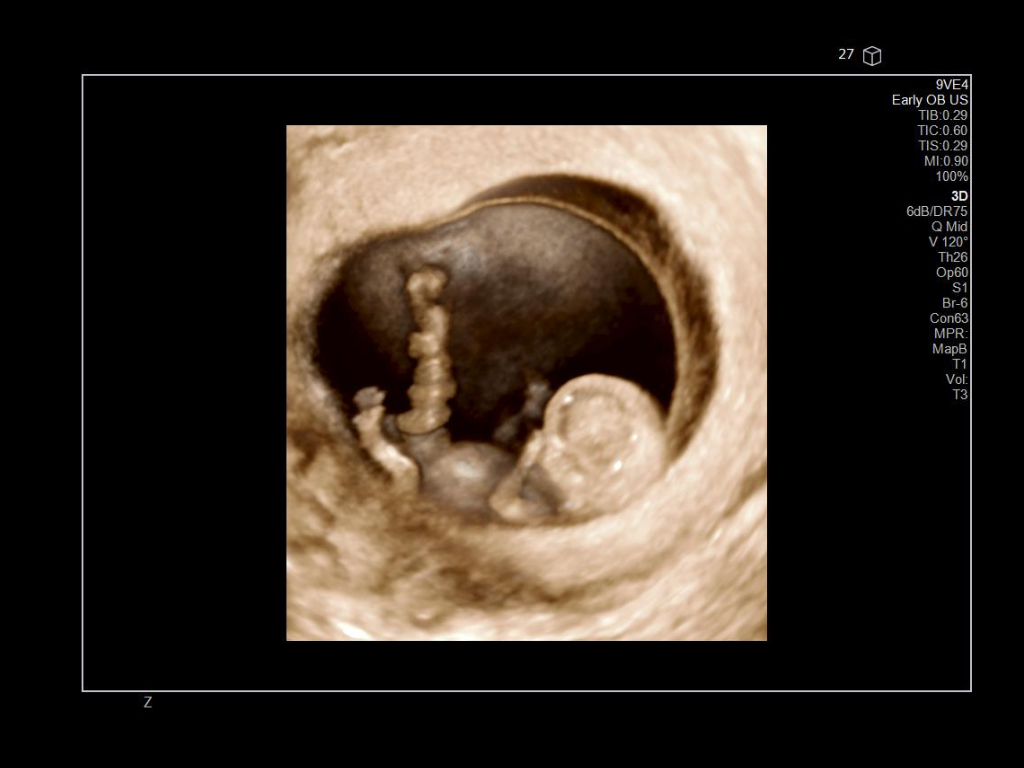

The ACUSON Sequoia is an advanced diagnostic tool that integrates cutting-edge technology and AI-powered applications to streamline diagnostic processes. This system is designed to cater to patient-specific needs, ensuring accuracy and efficiency in various clinical settings such as Radiology, OB/GYN, Shared Service and beyond.

The latest updates on ACUSON Sequoia use the power of groundbreaking AI for abdominal cases, includes advanced breast visualization to deliver new levels of image quality confidence, and tackles the toughest challenges in musculoskeletal imaging, all while saving your team from needless strain and pain.

A clearer, deeper perspective with optimal acoustics for each clinical use case. Expand your assessment with advanced tools that take ultrasound beyond its traditional role.